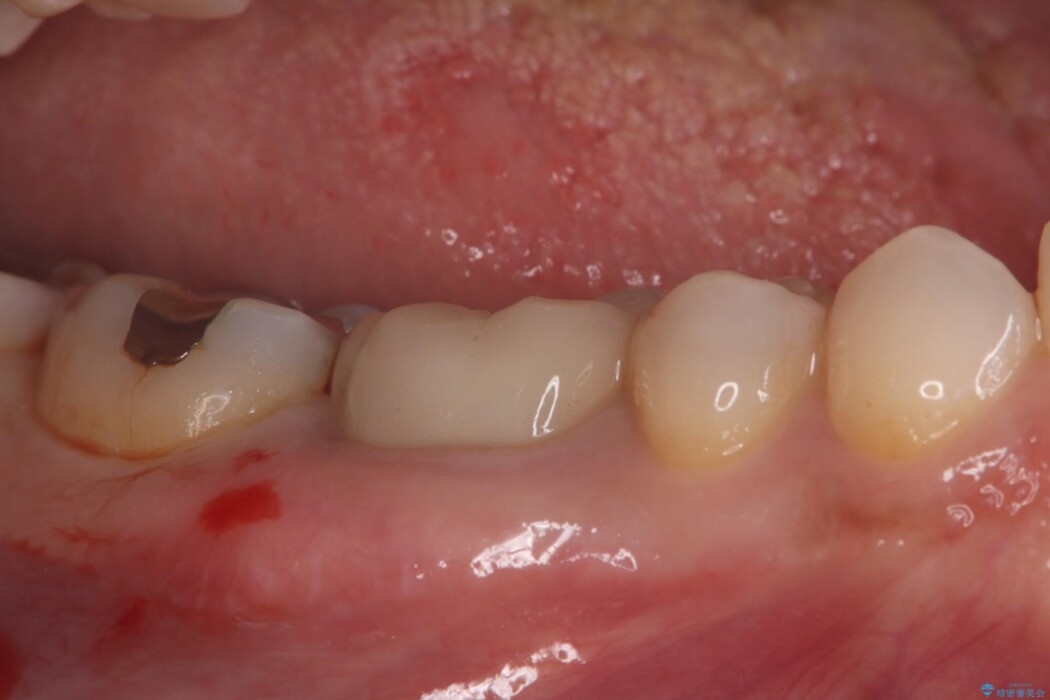

右下奥歯(7番)に違和感があるとご相談にいらっしゃった患者様です。

診査の結果、古い銀歯の隙間から新しい虫歯が広がっていました。ここは噛む力が強くかかる場所のため、このまま詰め物で治すと、部分的な詰め物では残存している自分の歯に負担が集中し、将来的に歯が割れてしまう「歯冠破折」のリスクが高い状態でした。